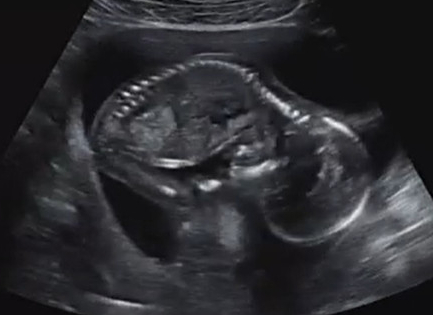

임신 20주차 0일, 태교여행 가기 전 압박스타킹 처방, 광복이 영상 기록

태교여행을 가기 전, 압박스타킹도 처방 받고 울 광복이도 잘 있나~ 산부인과를 방문했다. 임산부의 경우, ...